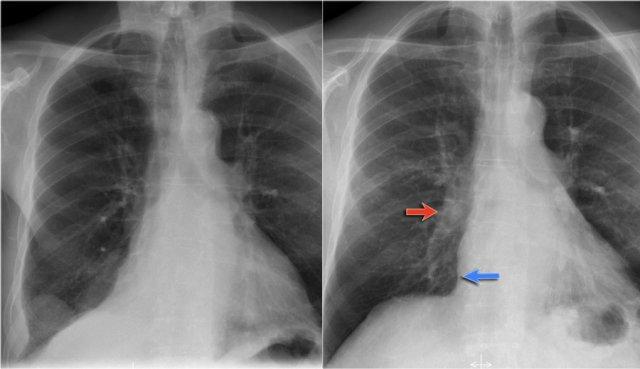

Bệnh nhân này có thuyên tắc phổi được phát hiện trên CT có thuốc cản quang (CECT).

Đông đặc ngoại vi được thấy ở vùng có thuyên tắc và có thể được quy cho xuất huyết trong vùng nhồi máu.

Lưu ý động mạch nuôi dưỡng phân nhánh từ động mạch chủ (mũi tên xanh).